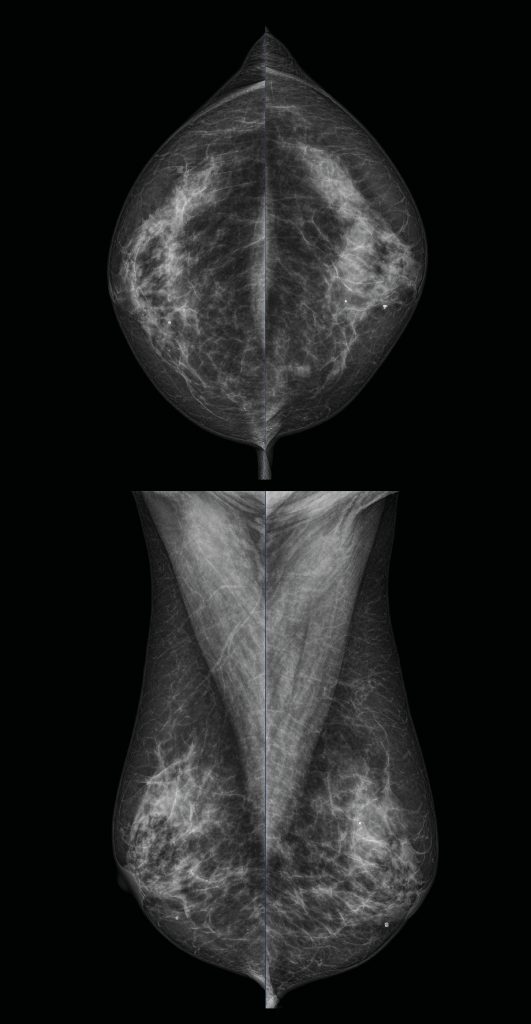

Digital Mammography with the most reliable digital mammography systems

MEDICAL SYSTEMS P.C. markets mammography systems of well-known foreign firms and equips diagnostic and medical centers, clinics and hospitals.We are beside you from the stage of research and study on the appropriate mammography system, supply, installation and maintenance over time.